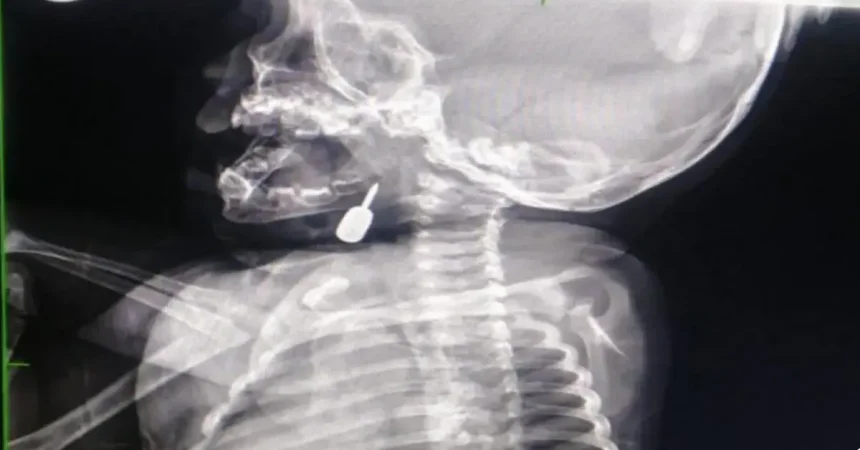

تمكّن أخصائي الأنف والأذن والحنجرة الدكتور محمود السبول من إجراء عملية _ فتح رغامى _ تُعد

الأولى من نوعها في مستشفى الملكة رانيا العبدالله، وقد تمت بنجاح.

وفي تدخل طبي عاجل، أنقذ الدكتور السبول حياة طفل يبلغ من العمر أحد عشر شهراً، بعد أن

وصل إلى قسم الطوارئ وهو يعاني من حالة اختناق حادة نتيجة وجود جسم معدني عالق في

منطقة الحنجرة. وقد تم استخراج الجسم بنجاح، مما أسهم في إنقاذ حياة الطفل.